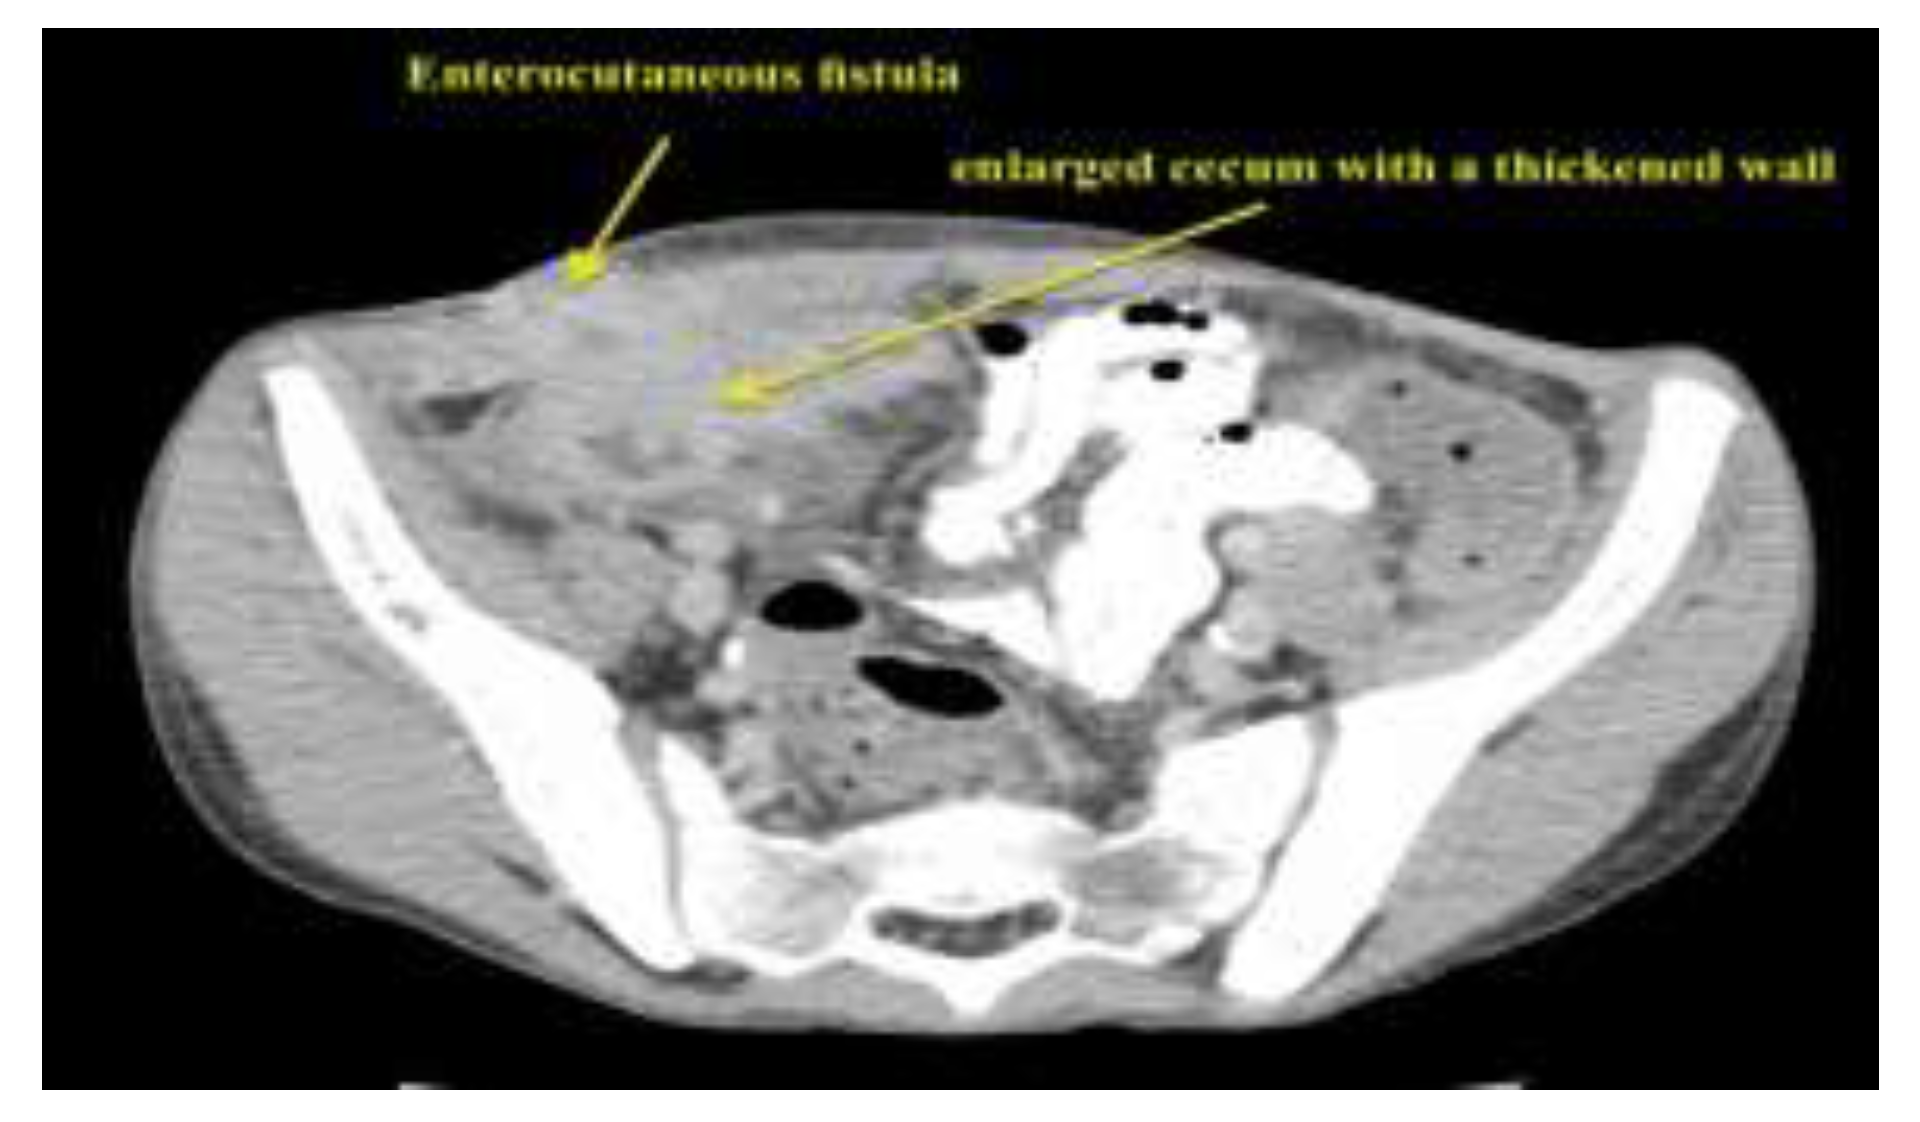

- The entero-cutaneous fistula is a severe postoperative complication of appendectomy. In rare cases, its underlying cause is granulomatous appendectomy – an initial manifestation of Crohn’s disease.

- The patient we present did not have any relevant history of Crohn’s disease. The histopathological examination of the appendix played an important role in the final diagnosis, accounting for the aggravating evolution of the patient who had undergone appendectomy.